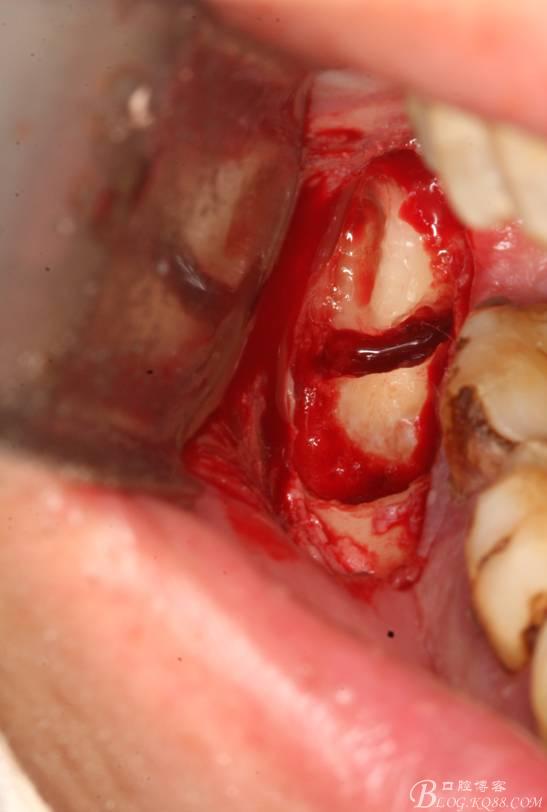

6.橫斷牙冠

7.取出牙冠